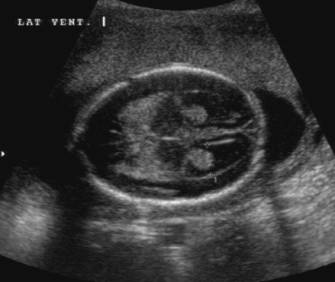

What is this an image of?

lobar holoprosencephaly